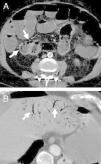

Neumatosis intestinal

Intestinal pneumatosis